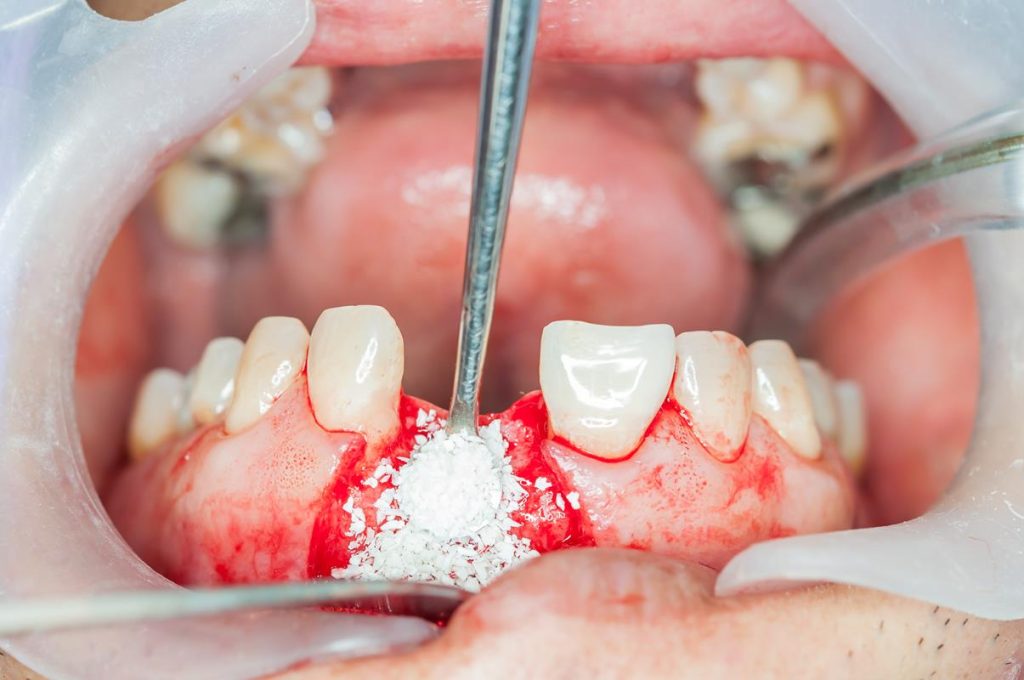

- Allograft: Bone sourced from a donor, typically obtained from certified bone banks. Donor bone is rigorously processed and sterilized, making it a safe and effective option.

Once the bone graft is placed, the area begins to heal and regenerate, allowing new bone to grow and integrate with the graft. This process helps restore both strength and structure to the jaw, making it possible to proceed with implant placement or other periodontal treatments.